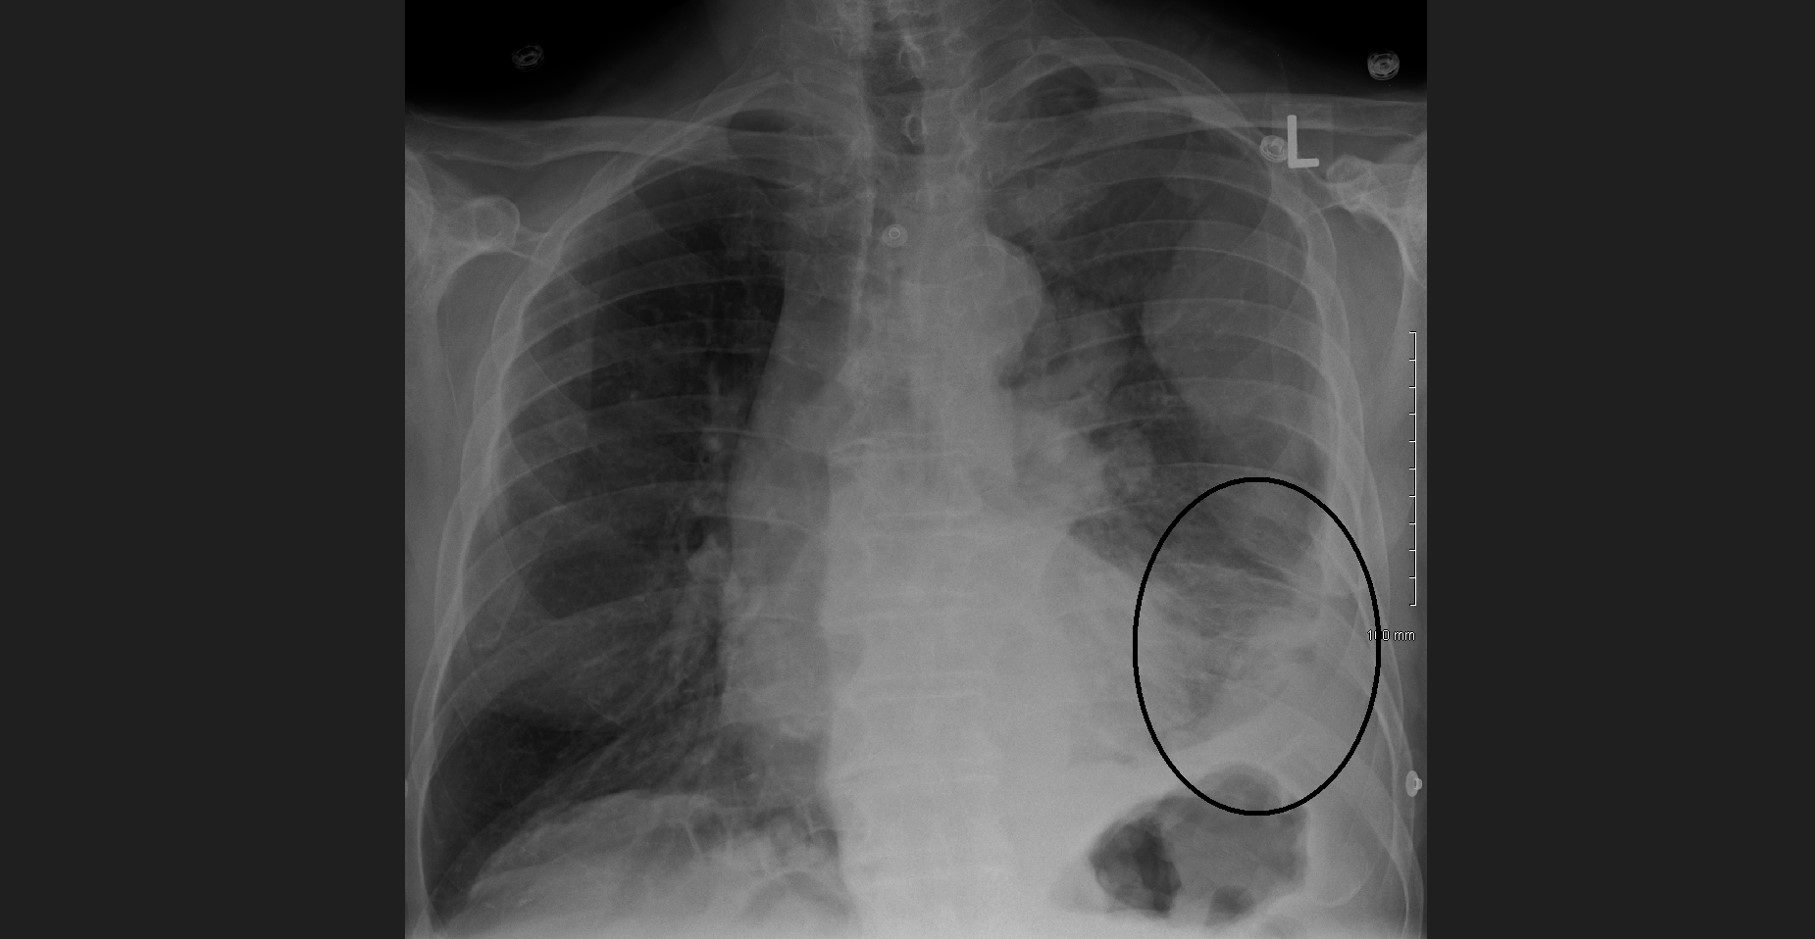

Causado pela exposição ao amianto (asbesto), o mesotelioma pleural maligno é um tipo de câncer raro, mas muito agressivo, com prognóstico de sobrevida de seis a 18 meses, o que torna necessária a identificação de novos marcadores preditivos e prognósticos para a doença.

Ela explica que a exposição às fibras do asbesto destrói as células mesoteliais normais da pleura, membrana que reveste o pulmão. A doença se desenvolve a partir do efeito combinado entre as células da pleura e os macrófagos (células de defesa) que fagocitam as fibras do asbesto.

A doença fica latente por um período e costuma aparecer após os 50 anos. Acomete mais homens do que mulheres, principalmente trabalhadores ou ex-funcionários de empresas que empregavam ou empregam asbesto em materiais como caixas d’água, telhas, forros, pisos e divisórias. A Organização Mundial da Saúde (OMS) emitiu alertas sobre o amianto, classificado como reconhecidamente cancerígeno e banido em diversos países, incluindo o Brasil, que só o proibiu em 2017, depois de anos de pressão das vítimas de doenças causadas pelo material, entre elas o mesotelioma pleural. Desde então, muitas vezes reunidos em associações, os afetados vêm processando empregadores.